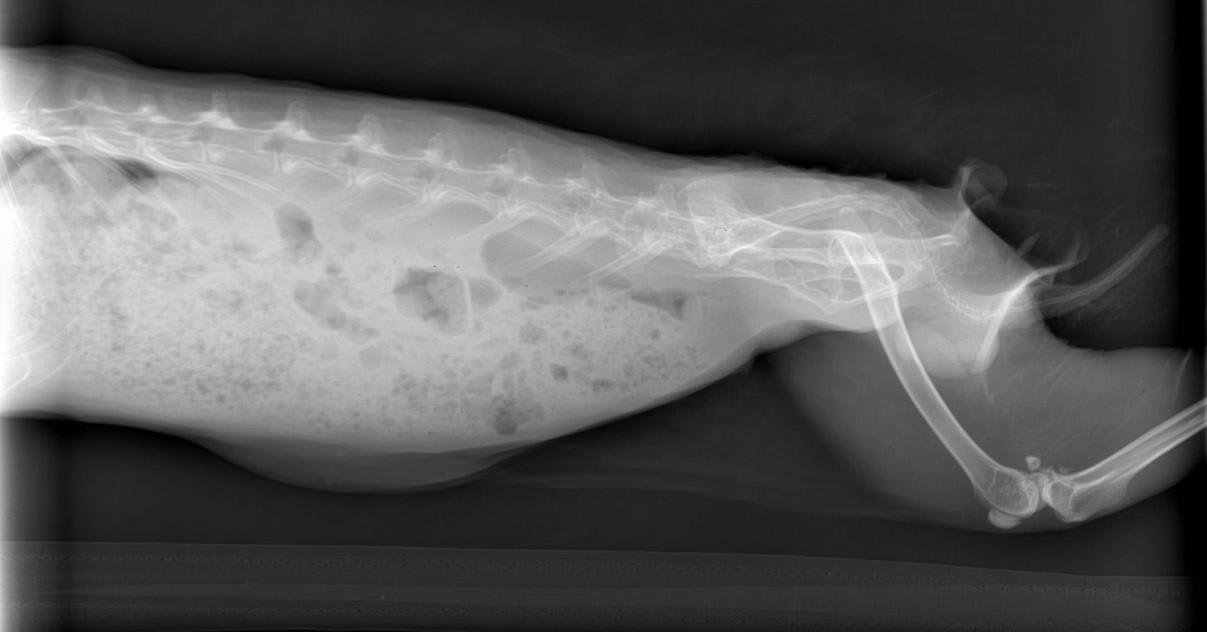

My rabbit's hind leg x-ray: Does it look normal to a veterinarian?

Pet's info: Small Animal | Rabbit | Female | spayed | 5 years and 2 months old | 4.1 lbs

Hello, I'd like someone to look at the xrays of my rabbit's hind leg and tell me if it looks normal.

Yes it seems normal to me but for full and thorough assessment another view of the leg (caudo cranial, or cranio caudal) should be ideally taken. Hope this answer was helpful, but please do not hesitate to contact us again on the forum or by requesting a consultation if you have any more questions or to discuss it any further.